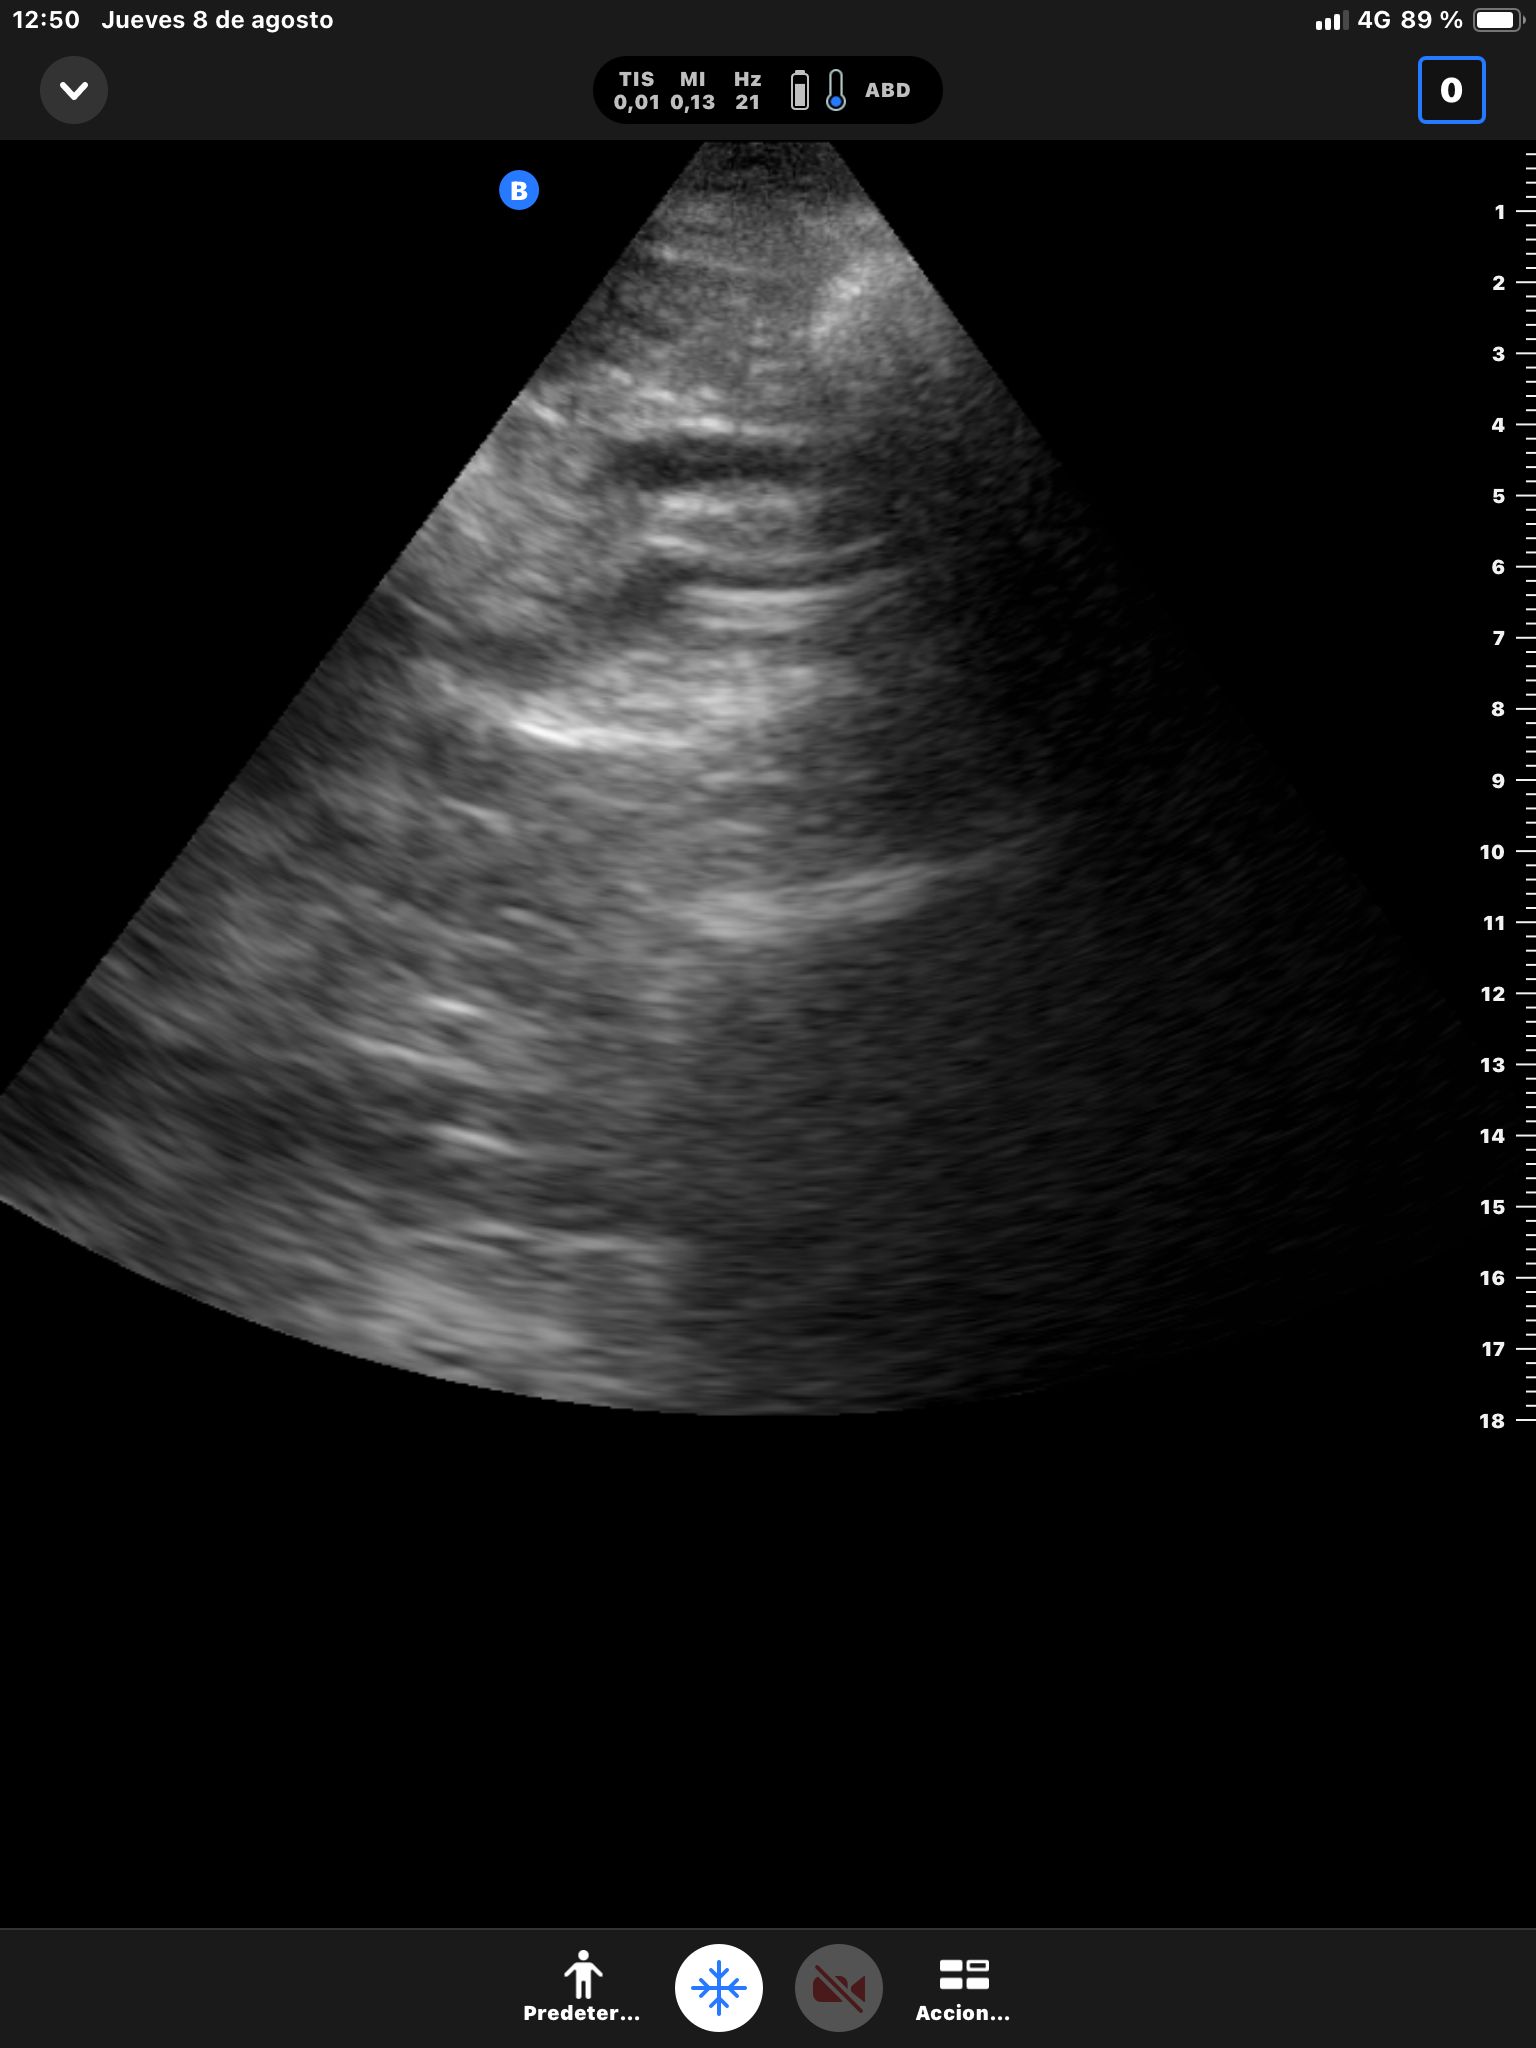

Hígado sin LOEs. Vesícula biliar con hidrops (58 mm), dilatación del colédoco (10 mm). Páncreas hiperecogénico, atrófico, Wirsung de 76 mm.

Dilatación de la vía biliar intrahepática con colédoco dilatado y atrapado por un área hipocaptante sobre la cabeza del páncreas. Atrofia del páncreas con dilatación del conducto de Wirsung que presenta calibres de hasta 8 mm con afilamiento o en el área de la cabeza pancreática.